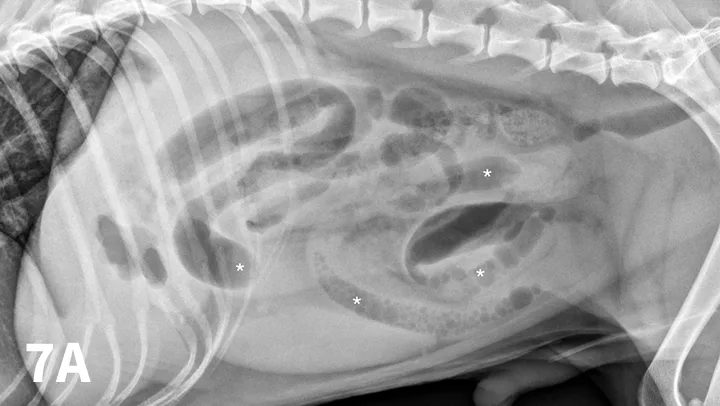

FIGURE 3A

Left lateral radiograph of a 4-year-old crossbreed dog with a history of vomiting. The patient was clinically stable. Granular, well-defined soft tissue opaque material is present within the fundus of the stomach, consistent with food or foreign material.

Food or ingesta can look similar to foreign material and can be difficult to differentiate. Depending on the presentation, radiography can be repeated after fasting period to document passage (or lack thereof) of GI content (Figures 3 and 4). Persistence of opaque foreign material in the same location over a 24- to 48-hour period should increase the suspicion of partial obstruction. In cases of complete mechanical obstruction, radiographic features of obstruction can develop during this time. This makes it easier to recognize the obstruction radiographically (Figure 4C).